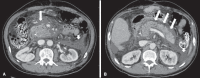

Acute pancreatitis is an inflammatory condition caused by intracellular activation and extravasation of inappropriate proteolytic enzymes determining destruction of pancreatic parenchyma and peripancreatic tissues. This is a fairly common clinical condition with two main presentations, namely, endematous pancreatitis - a less severe presentation -, and necrotizing pancreatitis - the most severe presentation that affects a significant part of patients. The radiological evaluation, particularly by computed tomography, plays a fundamental role in the definition of the management of severe cases, especially regarding the characterization of local complications with implications in the prognosis and in the definition of the therapeutic approach. New concepts include the subdivision of necrotizing pancreatitis into the following presentations: pancreatic parenchymal necrosis with concomitant peripancreatic tissue necrosis, and necrosis restricted to peripancreatic tissues. Moreover, there was a systematization of the terms acute peripancreatic fluid collection, pseudocyst, post-necrotic pancreatic/peripancreatic fluid collections and walled-off pancreatic necrosis. The knowledge about such terms is extremely relevant to standardize the terminology utilized by specialists involved in the diagnosis and treatment of these patients.